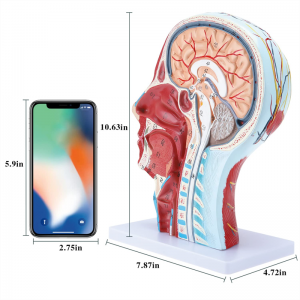

| Isem tal-Prodott | Kranju tal-bniedem b'mudell newrovaskulari tal-muskoli |

| Materjal | PVC |

| Dimensjoni | 21 * 12 * 27cm |

| Karatteristiċi | Il-mudell juri l-morfoloġija lokali tal-ġnub ta 'ġewwa u ta' barra tas-sezzjoni sagittali medjana tar-ras u tal-għonq, kif ukoll l-istrutturi tal-bastimenti tad-demm u n-nervituri, u hemm 84 partijiet li jindikaw sinjali b'kollox. |

【1: 1 Lifesize】 Sezzjoni medjana ta '1: 1 Natural Head & Neck Mudell tal-muskolu vaskulari newrali superfiċjali (naħa tal-lemin). Xogħol sabiħ. Toffri firxa sħiħa ta 'karatteristiċi anatomiċi.